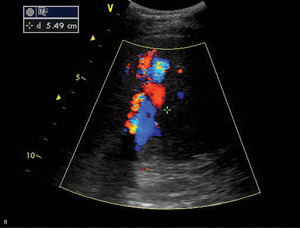

Optymalną metodą w rozpoznawaniu przyczyny nadciśnienia wrotnego jest color doppler. Jest to metoda tania, nieinwazyjna i powszechnie dostępna. Umożliwia przy tym wszechstronną ocenę: uwidacznia zarówno zmiany miąższowe, jak i zaburzenia przepływu w naczyniach (skrzepliny w obrębie naczyń, uciśnięcie naczyń lub nacieczenie przez rozrost nowotworowy; daje możliwość uwidocznienia dróg krążenia obocznego, naczyń tętniczych, żył wątrobowych i krążenia wrotnego). Pulsed wave doppler pozwala na ocenę kierunku i charakteru przepływu: uwidocznienie naczyń i przetok tętniczo-żylnych jest bardzo dobre (ryc. 1).